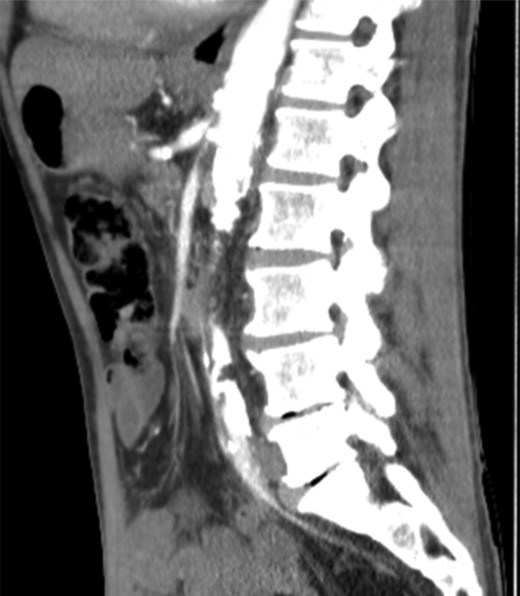

Gastroscopy revealed a benign duodenal stricture between D1 and D2, which subsequently resolved on treatment. An abdominal CT scan identified a lesion in the right lobe of the liver deemed benign on further CT assessment with triple-phase contrast. However, the latter also revealed heavy calcification throughout the abdominal aorta with severe stenosis at the origins of the coeliac axis, bilateral renal, superior mesenteric and inferior mesenteric arteries (Fig. 1).

CT angiography—heavy calcification through abdominal aorta and severe stenosis of coeliac axis, renal arteries, SMA and IMA.